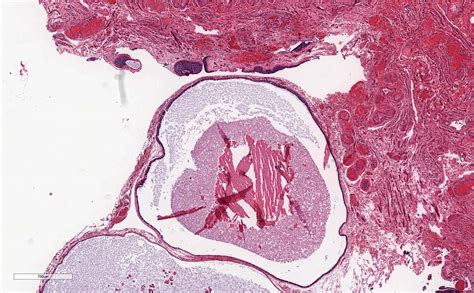

• gartner's duct cyst pathology

• gartner's duct cyst pathology outlines